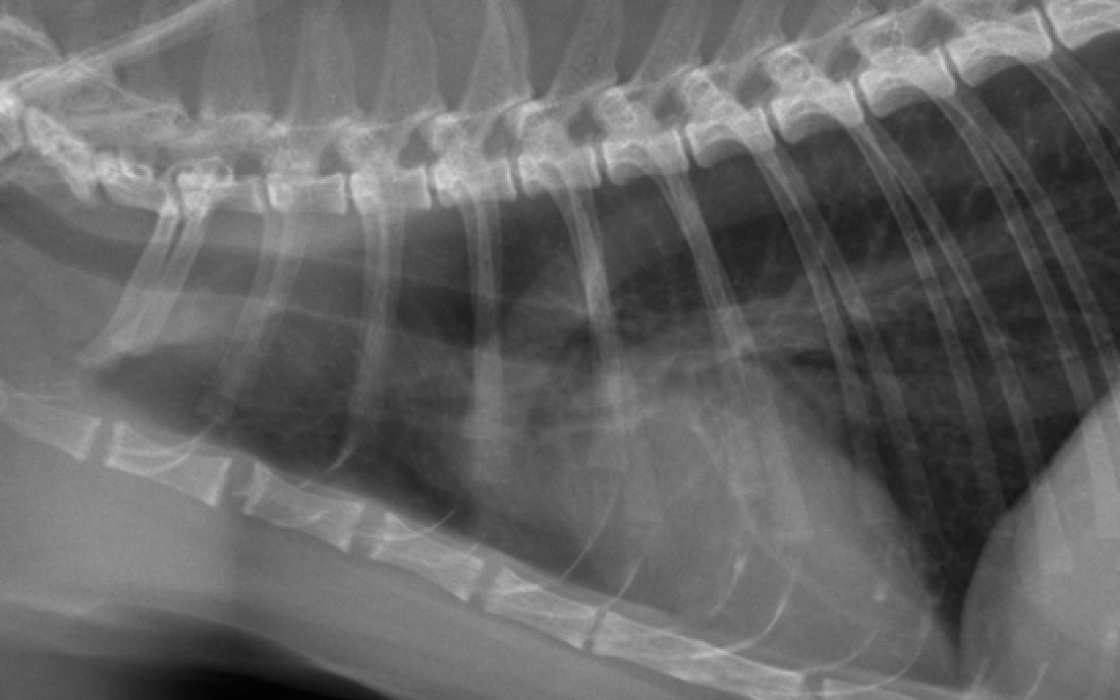

Nouvelle technique pour le traitement chirurgical de la rupture du ligament croisé crânial chez le chien et le chat avec un implant synthétique à fibres libres

Plusieurs études anatomiques ont montré qu’il existe un point isométrique sur la face interne du condyle externe (2), qui se situe au centre de l’arc-de-cercle de 140° formé par la partie postérieure du condyle externe. La technique chirurgicale mise au point permet de placer le ligament synthétique dans cette zone isométrique du fémur, afin de limiter les variations de longueur de l’implant dans l’articulation entre la flexion et l’extension, et ainsi réaliser une reconstruction physiologique sans modifier l’architecture du grasset : seulement 4 tunnels osseux sont réalisés.